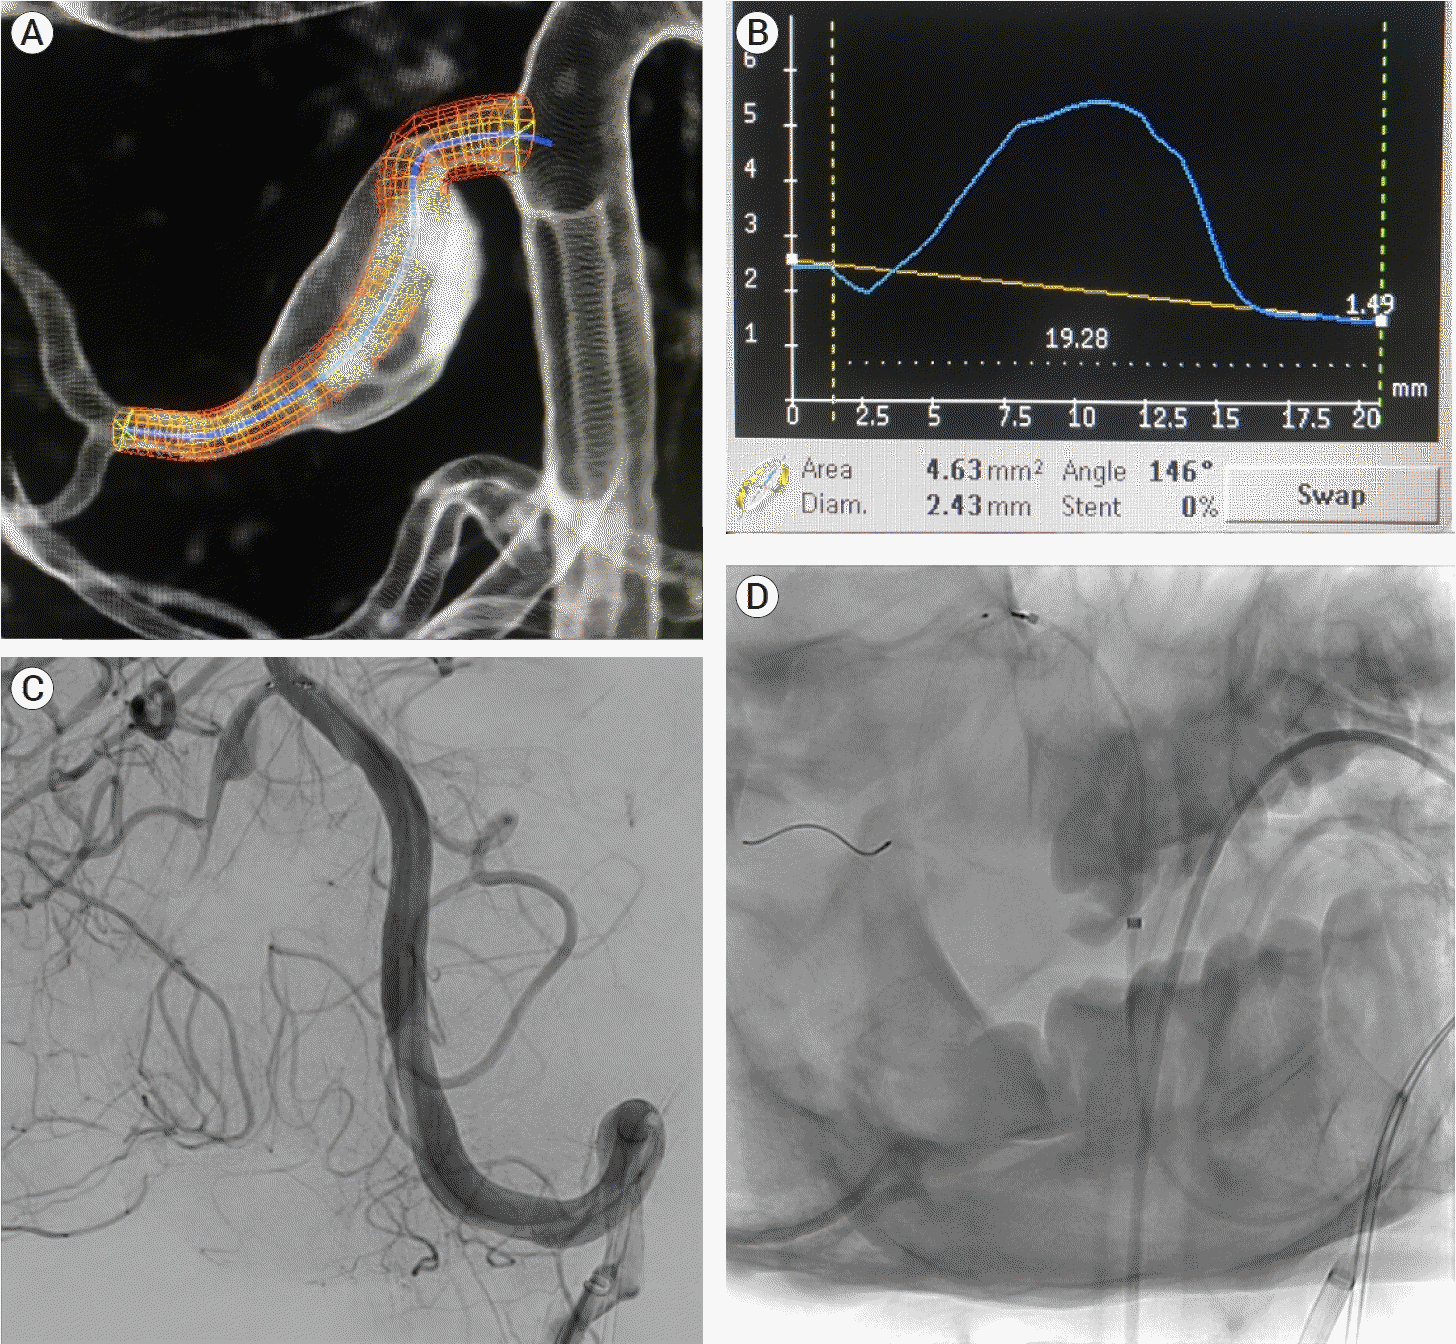

The patient was given aspirin 81 mg and clopidogrel 75 mg daily for three days before the procedure. A right common femoral artery puncture was performed and an 8F sheath was inserted after general anesthesia, neuromuscular paralysis, and endotracheal intubation. Using a roadmap and guidewire technique, a Neuron Max 088 support catheter (Penumbra, USA) was advanced to the left vertebral artery. The right AICA-PICA common trunk arose at a sharp angle from the midportion of the basilar artery. The Asahi Intecc micro-guidewire (USA), which provided adequate microcatheter support strength, was used to enter the trunk. The micro-guidewire and microcatheter system (Phenom plus catheter co-axial with Phenom 27 catheter) were advanced past the aneurysm into the AICA-PICA trunk’s inferior bifurcation, which supplied the distal PICA territory. This 1.25 mm-diameter segment was chosen as the flow diverting stent’s distal landing zone. The proximal landing zone, which measured 1.5 mm in diameter, was chosen as the segment between the beginning of the aneurysm and the origin of the AICA-PICA trunk at the basilar artery. The smallest PED-Shield available is 2.5 mm in diameter. As a result, a 2.5 mm×14 mm PED-Shield was successfully deployed without incident (Fig. 4). Final angiograms revealed that the stent was well-positioned, covering the entire neck of the aneurysm, with parent vessel patency (Fig. 5). The patient awoke neurologically intact from endovascular intervention and had an uneventful post-operative period. On post-operative day 2, he was discharged home.

Fig. 4.

Planning of stent deployment (A and B). Selective cannulation of the right AICA-PICA variant (C) and stent deployment covering the fusiform aneurysm on its entire length (D). AICA, the anterior inferior cerebellar artery; PICA, posterior inferior cerebellar artery